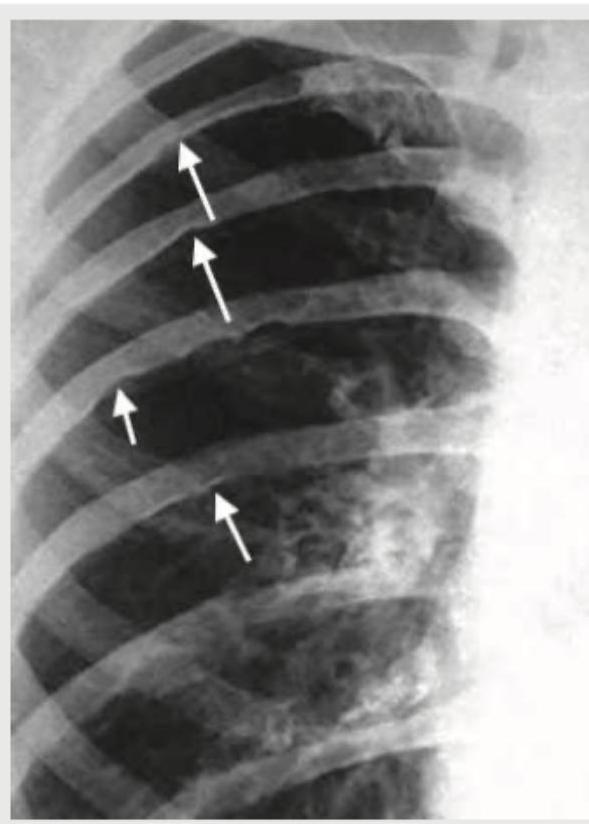

A short stature female presents with history of wearing socks in summer season. Physical examination shows icy cold toes with cyanosis. CXR done shows:

Explanation: ***Coarctation of aorta*** - The imaging provided illustrates **rib notching**, a classic radiographic sign caused by erosion of the inferior rib margins by enlarged intercostal arteries. This occurs as these arteries develop collateral circulation to bypass the narrowed aorta in **coarctation of the aorta**. - **Short stature** and **icy cold toes with cyanosis** are also consistent with coarctation of the aorta. The reduced blood flow to the lower extremities causes peripheral cyanosis and coldness, while reduced overall growth can lead to short stature. *Hyperparathyroidism* - This condition primarily affects **calcium and phosphate metabolism**, leading to bone resorption and potential features like subperiosteal bone erosion, brown tumors, and osteopenia. - It does not typically cause rib notching or the peripheral vascular symptoms described. *Neurofibromatosis* - Neurofibromatosis is a genetic disorder affecting **nerve tissue growth**, - It's associated with neurofibromas, café-au-lait spots, and Lisch nodules. While it can cause some skeletal abnormalities, **rib notching** as a primary feature is not typical, and the described peripheral vascular symptoms are not characteristic. *Multiple myeloma* - This is a **plasma cell malignancy** characterized by monoclonal immunoglobulin production, leading to lytic bone lesions, hypercalcemia, renal failure, and anemia. - While it affects bones and can produce lytic lesions in the ribs, it does not cause the characteristic **inferior rib notching** seen in the image, nor does it typically present with peripheral cyanosis and cold extremities directly related to a vascular obstruction.

Explanation: ***Postductal coarctation*** - The image shows **rib notching** (highlighted by the arrow), a classic sign of **collateral vessel development** due to narrowing of the aorta **distal to the ductus arteriosus**. - This congenital heart defect is associated with **hypertension** in the upper extremities and can lead to symptoms like **headaches**. *Preductal coarctation* - This typically presents earlier in life, often with **heart failure** in infancy, and is less commonly associated with **hypertension** and **rib notching** in a seemingly asymptomatic adult. - The coarctation is located **proximal to the ductus arteriosus**, leading to different collateral circulation patterns. *Aortic dissection* - This condition is an acute medical emergency characterized by a tear in the **aortic wall**, often presenting with sudden, severe chest or back pain. - CXR findings typically include a **widened mediastinum**, not specifically rib notching. *Takayasu arteritis* - This is a **granulomatous vasculitis** primarily affecting the aorta and its major branches, leading to narrowing or occlusion. - While it can cause hypertension, **rib notching** is not a characteristic radiological finding; signs usually include vessel wall thickening or stenoses.